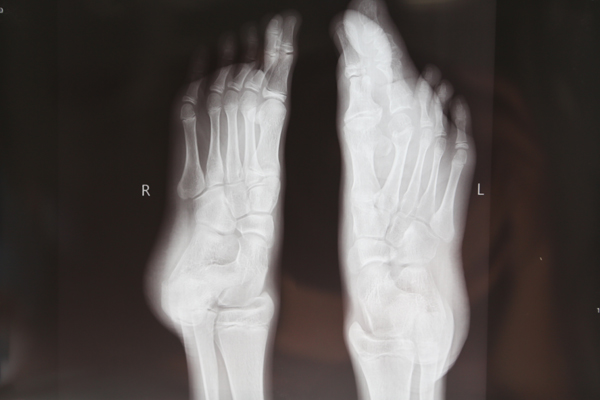

在小东4岁时,他父母就发现小东的左脚大拇指与二拇指比其他脚趾长,当时还没太在意,随着年龄的增长,那两个脚指头明显的比其他脚指头长的快,已经长长的超出的其他脚指头。这给活泼的小东带来很大的烦恼,他再也不敢光着脚丫和小朋友玩了,因为大家会笑他;每次洗脚时都偷偷的藏一边,怕别人看见;每次自己看见那丑陋的脚趾,就想用刀把他砍掉算了。在生活中,无论是走路、还是跑步时,稍不注意,脚抬的低点,大脚趾就会碰地,痛的钻心,而且经常不小心就摔倒。这二个大脚指头给小东带来了很多的烦恼……

小东的父母带他找到了交大二院贺西京教授,经诊断,小东患的是一种罕见的巨趾(指)症。巨趾症是神经生长异常所致,以手指或足趾体积增大为特征的先天性畸形,在四肢先天性畸形中的发生率很低,约为0.9%。表现为某肢体软组织和骨组织均匀增大,体积为正常肢体体积的5倍。畸形生长给患者心理带来压力和痛苦,生活失去自信,严重影响患者的生活质量。贺教授接诊后,带领治疗小组仔细检查,研究小东的影像资料,制定慎密的手术治疗方案。确保功能,防止坏死,纠正外观… 于7月27日成功的为小东施行了巨指畸形矫正术。掰掉了左脚第二趾,重塑脚趾。解除了小东及其父母的烦恼。看着变得美观、好看的脚趾,小东开心的笑了。